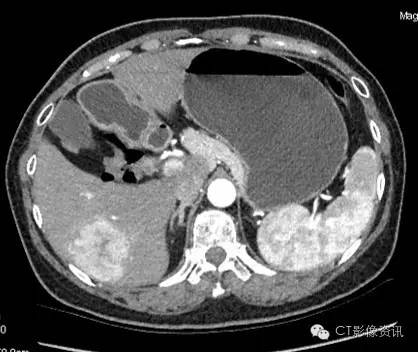

各期扫描及CT值测定 平扫

病灶内CT值:55.13

动脉期

病灶内CT值:160.26

静脉期

病灶内CT值:144.22